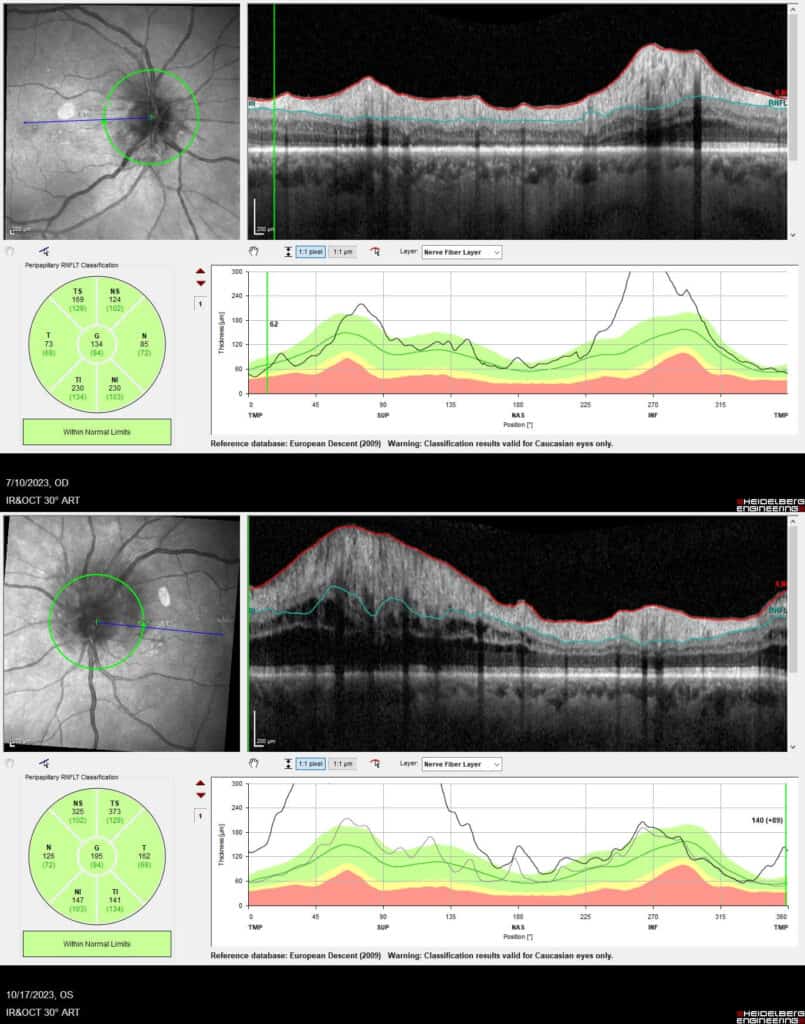

One month later, the left eye acuity worsened to 20/200 and there was a 1+ left afferent pupillary defect with markedly more disc edema to involve the nerve entirely (Figure 6). Over the course of multiple visits, the right optic nerve edema continued to improve leaving mild superior disc pallor with a final acuity of 20/25, dense inferior altitudinal field loss and significant nerve fiber layer thinning of the superior half of the nerve. The left optic nerve edema lessened at subsequent visits; the final acuity was 20/200 with overall peripheral loss and a 2+ left afferent pupillary defect. Interestingly, the left eye also developed subretinal fluid throughout the macula with residual outer retinal disruption which eventually resolved (Figure 7). Primary care and nephrology adjusted his hypertensive medications multiple times, which proved challenging given hypertensive episodes after medication reductions.

Figure 6. Disc photo (Left) and OCT imaging (Right) of OS at four months from initial visit show significant disc edema and worse compared to one month prior.